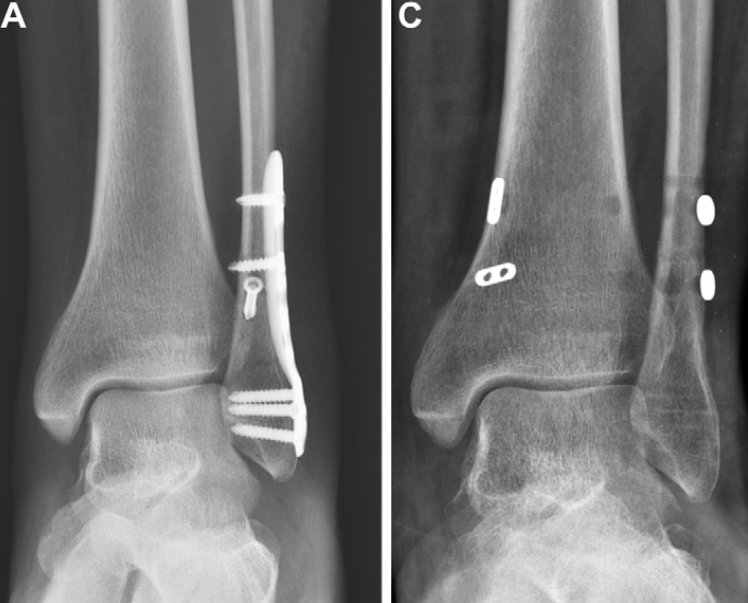

手术治疗

对于合并骨折的不稳定性胫腓联合损伤,需行切开复位内固定术,必要时进行韧带重建,重建部位通常为下胫腓前韧带和下胫腓后韧带。通过经胫腓联合螺钉固定进行刚性加压固定,或采用缝线纽扣技术进行动态固定,均可实现远端胫腓关节的加压稳定。目前,针对不稳定性远端胫腓关节手术干预的明确推荐仍面临挑战,原因在于相关研究较少,且骨折相关的研究数据存在矛盾。

螺钉固定

螺钉固定是治疗胫腓联合不稳的传统主流方法,但2010年代初,缝线纽扣技术因疗效良好逐渐受到关注,螺钉固定的应用也随之减少。然而,缝线纽扣技术无法完全恢复胫腓联合的稳定性,尤其在纵向和旋转平面,这一不足使得螺钉固定再次成为手术治疗的研究重点。目前已有大量文献支持,对于胫腓关节严重不稳、Maisonneuve骨折或不适于骨性固定的高位腓骨骨折,以及其他合并纵向移位的损伤,螺钉固定是优选的治疗方法。

缝线纽扣技术

1999年,首次有文献报道柔性胫腓联合固定装置的应用,其设计目的是在维持关节稳定性的同时,保留远端胫腓关节的生理活动。此后,缝线纽扣装置彻底改变了胫腓联合损伤的手术治疗格局,成为外科医生的标准治疗选择。近期的随机对照试验和系统综述表明,与螺钉固定相比,缝线纽扣技术具有优势,但相关研究的异质性较高。对于无骨折的韧带性不稳,柔性植入物是最合理的治疗选择。部分病例中,需联合使用缝线纽扣与螺钉固定,或进行韧带加强,才能完全恢复胫腓关节的稳定性。

02

术后并发症

与术前评估相似,术后评估也主要依靠影像学表现:术后即刻影像学检查用于确认植入物位置和骨折复位效果;随访X线片则用于观察骨折愈合情况,确认胫腓联合复位的维持状态。当怀疑骨性不愈合或持续性不稳时,CT检查具有重要价值;当患者术后出现疼痛,尤其怀疑存在持续性韧带缺损和/或肌腱异常时,可采用MRI检查。约15%的患者会发生术后并发症,其中39%表现为胫腓联合愈合不良,多数病例由初始复位不足所致;4%的手术干预会发生感染并发症。

刚性螺钉固定带来的生物力学负荷,会引发多种并发症,包括胫腓联合复位不良、螺钉松动、螺钉移位和螺钉断裂,这些并发症均可能需要取出螺钉:

上述并发症可能无明显的临床症状,从而延误对疼痛性螺钉或持续性胫腓联合不稳的发现和干预。放射科医生需在影像学检查中识别这些异常并予以提示,但同时也应注意,若胫腓联合已实现良好的愈合复位,螺钉周围的松动或螺钉断裂可能无临床症状,甚至提示胫腓联合的生理活动已部分恢复。